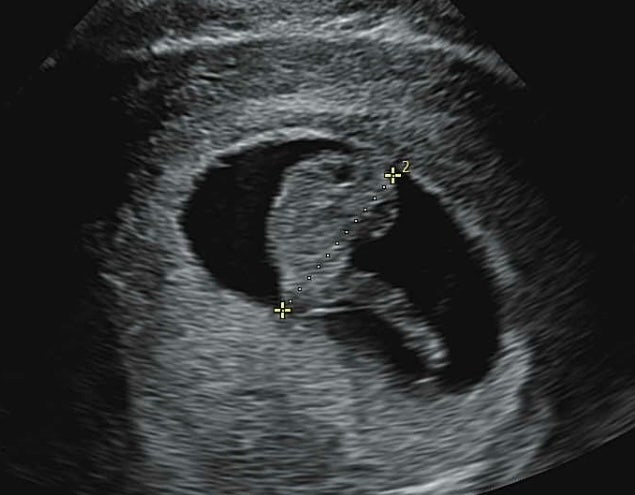

임신 6개월 7개월 정밀 초음파/임당 검사 통과

임신 중기 6개월 7개월 #정밀초음파 #임당 벌써 두콩이가 생긴지 7개월~~ 초기에는 시간이 너무 안 간다 싶...

12주 16주 1차 2차 기형아 검사 결과 / 성별확인 실패

벌써 두콩이가 16주가 넘어서 드디어 성별!! 그리구 기형아 검사를 완료했다 ㅎㅎ 12주차 1차 기형아 검사 ...